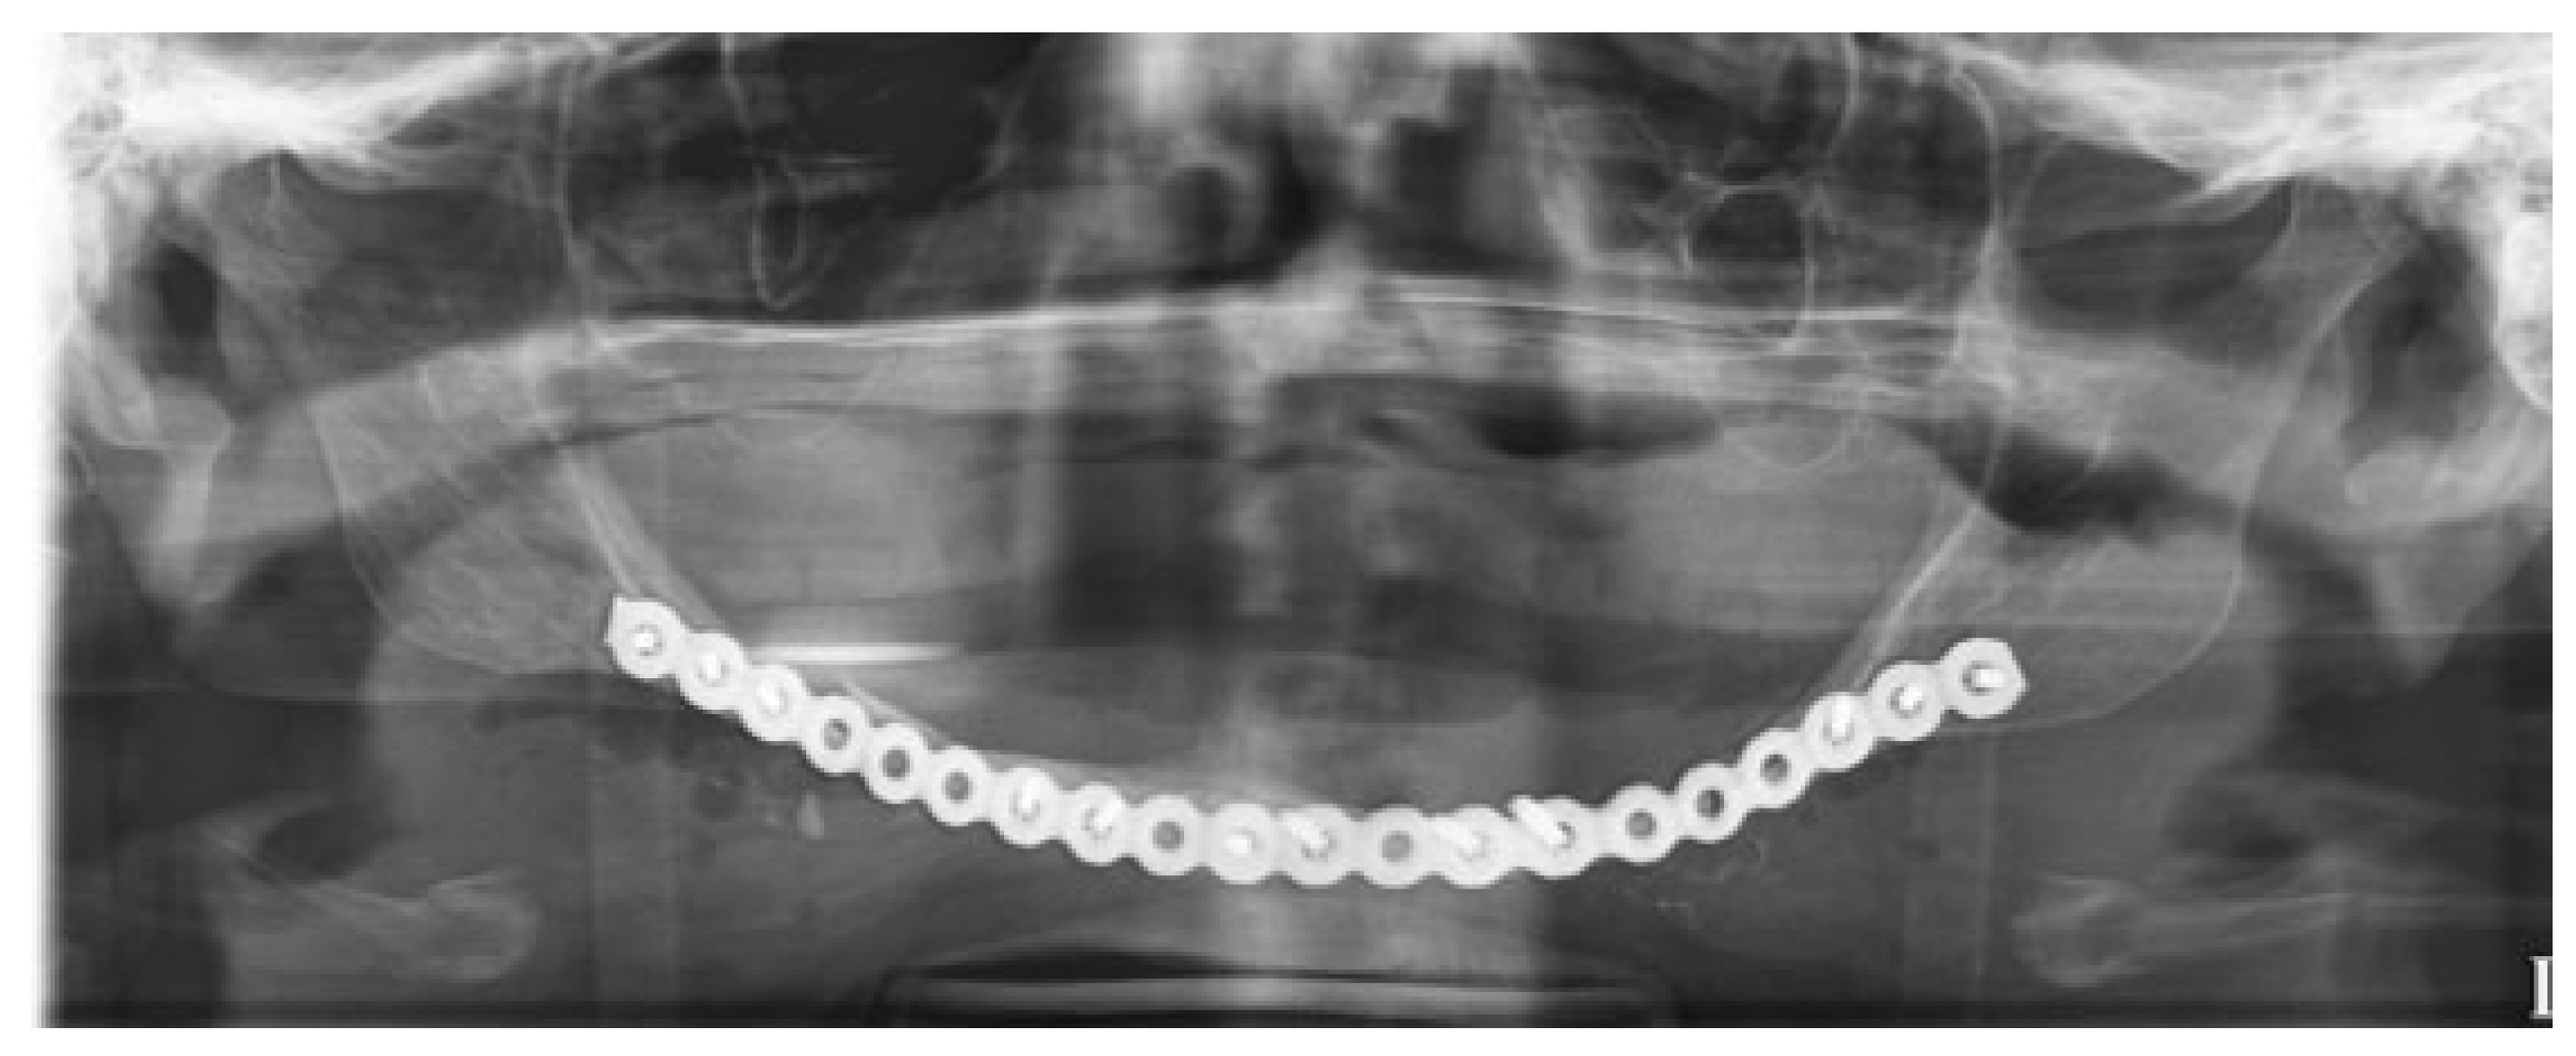

An extended submandibular approach was used and the mandible was exposed from angle to angle. The prebent plate was utilized to aid in the alignment of the segments and multiple bicortical locking screws were used (Figure 5). Multiple small fragments of bone were removed, the fracture sites were then debrided, and allograft (DBX Demineralized Bone Matrix–Musculoskeletal Transplant Foundation, Edison, NJ) was placed into the fracture sites. Layered closure was then performed (Figure 6). A postoperative panoramic radiograph showed good reduction of the fractures, intact hardware, and good plate adaptation (Figure 7). The patient was discharged on postoperative day 1. She was seen at 2 weeks and 6 months postoperatively and her injury healed well without complications.

Figure 7. Postoperative panoramic radiograph post open reduction and internal fixation of mandible fracture. Fracture is reduced well, and hardware is intact with excellent adaptation.